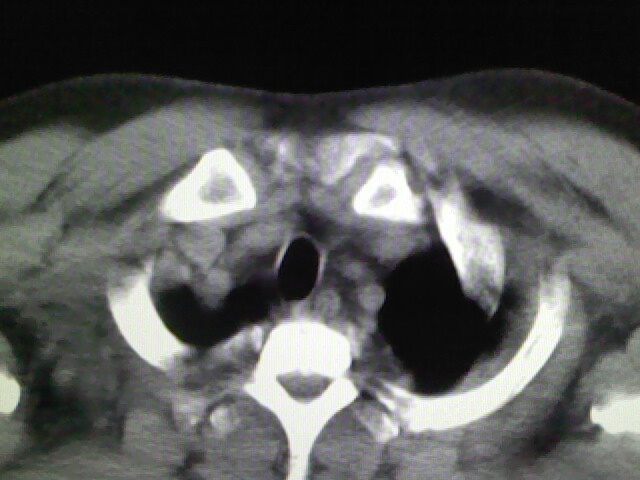

标题: CT17932:临床怀疑肺栓塞

男,34岁,自觉右侧胸痹,胸闷3天余

左上肺局限片状透光度增强区,肺纹理稀少,可考虑局限性肺气肿。

右侧肺动脉似见密度稍低影,请在机器的薄层上再看看有没有充盈缺损。

左上肺局限性肺透光度减低,肺纹理稀少;这虽然符合早期肺栓塞的改变,但与局限性肺气肿难以鉴别。

书上讲早期肺栓塞就是表现肺透光度减低,肺纹稀少。